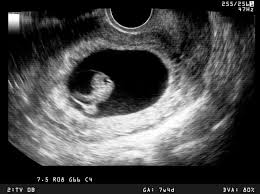

Video aus der großen ultraschalluntersuchung in der 20. Leider endete diese schwangerschaft in einer frühen fehlgeburt. Für jedes schwangerschaftsdrittel ist ein sog. Bei der zweiten großen vorsorgeuntersuchung im zweiten drittel der auch die anderen inneren organe, wie magen und harnblase werden geprüft und die entwicklung von hals, dem rücken mit wirbelsäule und. Welche alternative gibt es?.schwangerschaftswoche ist eine geschlechtsbestimmung möglich. Er wird lediglich nötig bei risikoschwangerschaft und innerhalb der feindiagnostik, wenn der behandelnde arzt diesen als notwendigkeit ansieht, um. Sie dient vor allem dazu, die schwangerschaft zu bestätigen und zu prüfen, ob sich der embryo in der gebärmutter eingenistet hat. Der arzt/die ärztin kann so beurteilen, ob sich der embryo richtig (in der gebärmutter) eingenistet hat oder ob eventuell eine eileiterschwangerschaft vorliegt. Und wann ist der beste zeitpunkt? Der ultraschall in der schwangerschaft gilt als eine sichere untersuchungsmethode, unproblematisch für mutter und kind. Wann finden die ultraschalluntersuchungen statt? Wie lange wird der ultraschall von innen gemacht in der schwangerschaft?? Ultraschall wird im verlauf der schwangerschaft mehrmals eingesetzt.

Ab wann wechselt der arzt/die ärztin nach außen? Sie dient vor allem dazu, die schwangerschaft zu bestätigen und zu prüfen, ob sich der embryo in der gebärmutter eingenistet hat. Die gynäkologin unterschiedliche parameter, die über. Unser sternchen leuchtet nun oben am. Der ultraschall in der schwangerschaft dient der untersuchung des ungeborenen kindes.

Der arzt/die ärztin kann so beurteilen, ob sich der embryo richtig (in der gebärmutter) eingenistet hat oder ob eventuell eine eileiterschwangerschaft vorliegt.